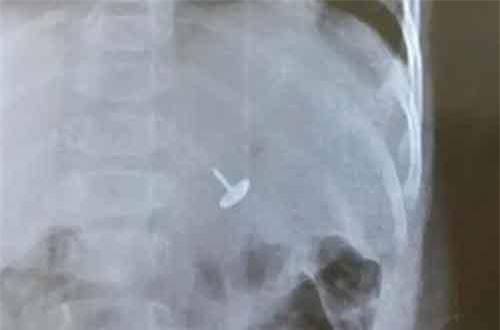

Ngay sau khi phát hiện con trai 11 tháng tuổi nuốt dị vật là một chiếc đinh vít dài, gia đình vội đưa trẻ đến Trung tâm y tế huyện Tiên Yên, tỉnh Quảng Ninh khám cấp cứu.